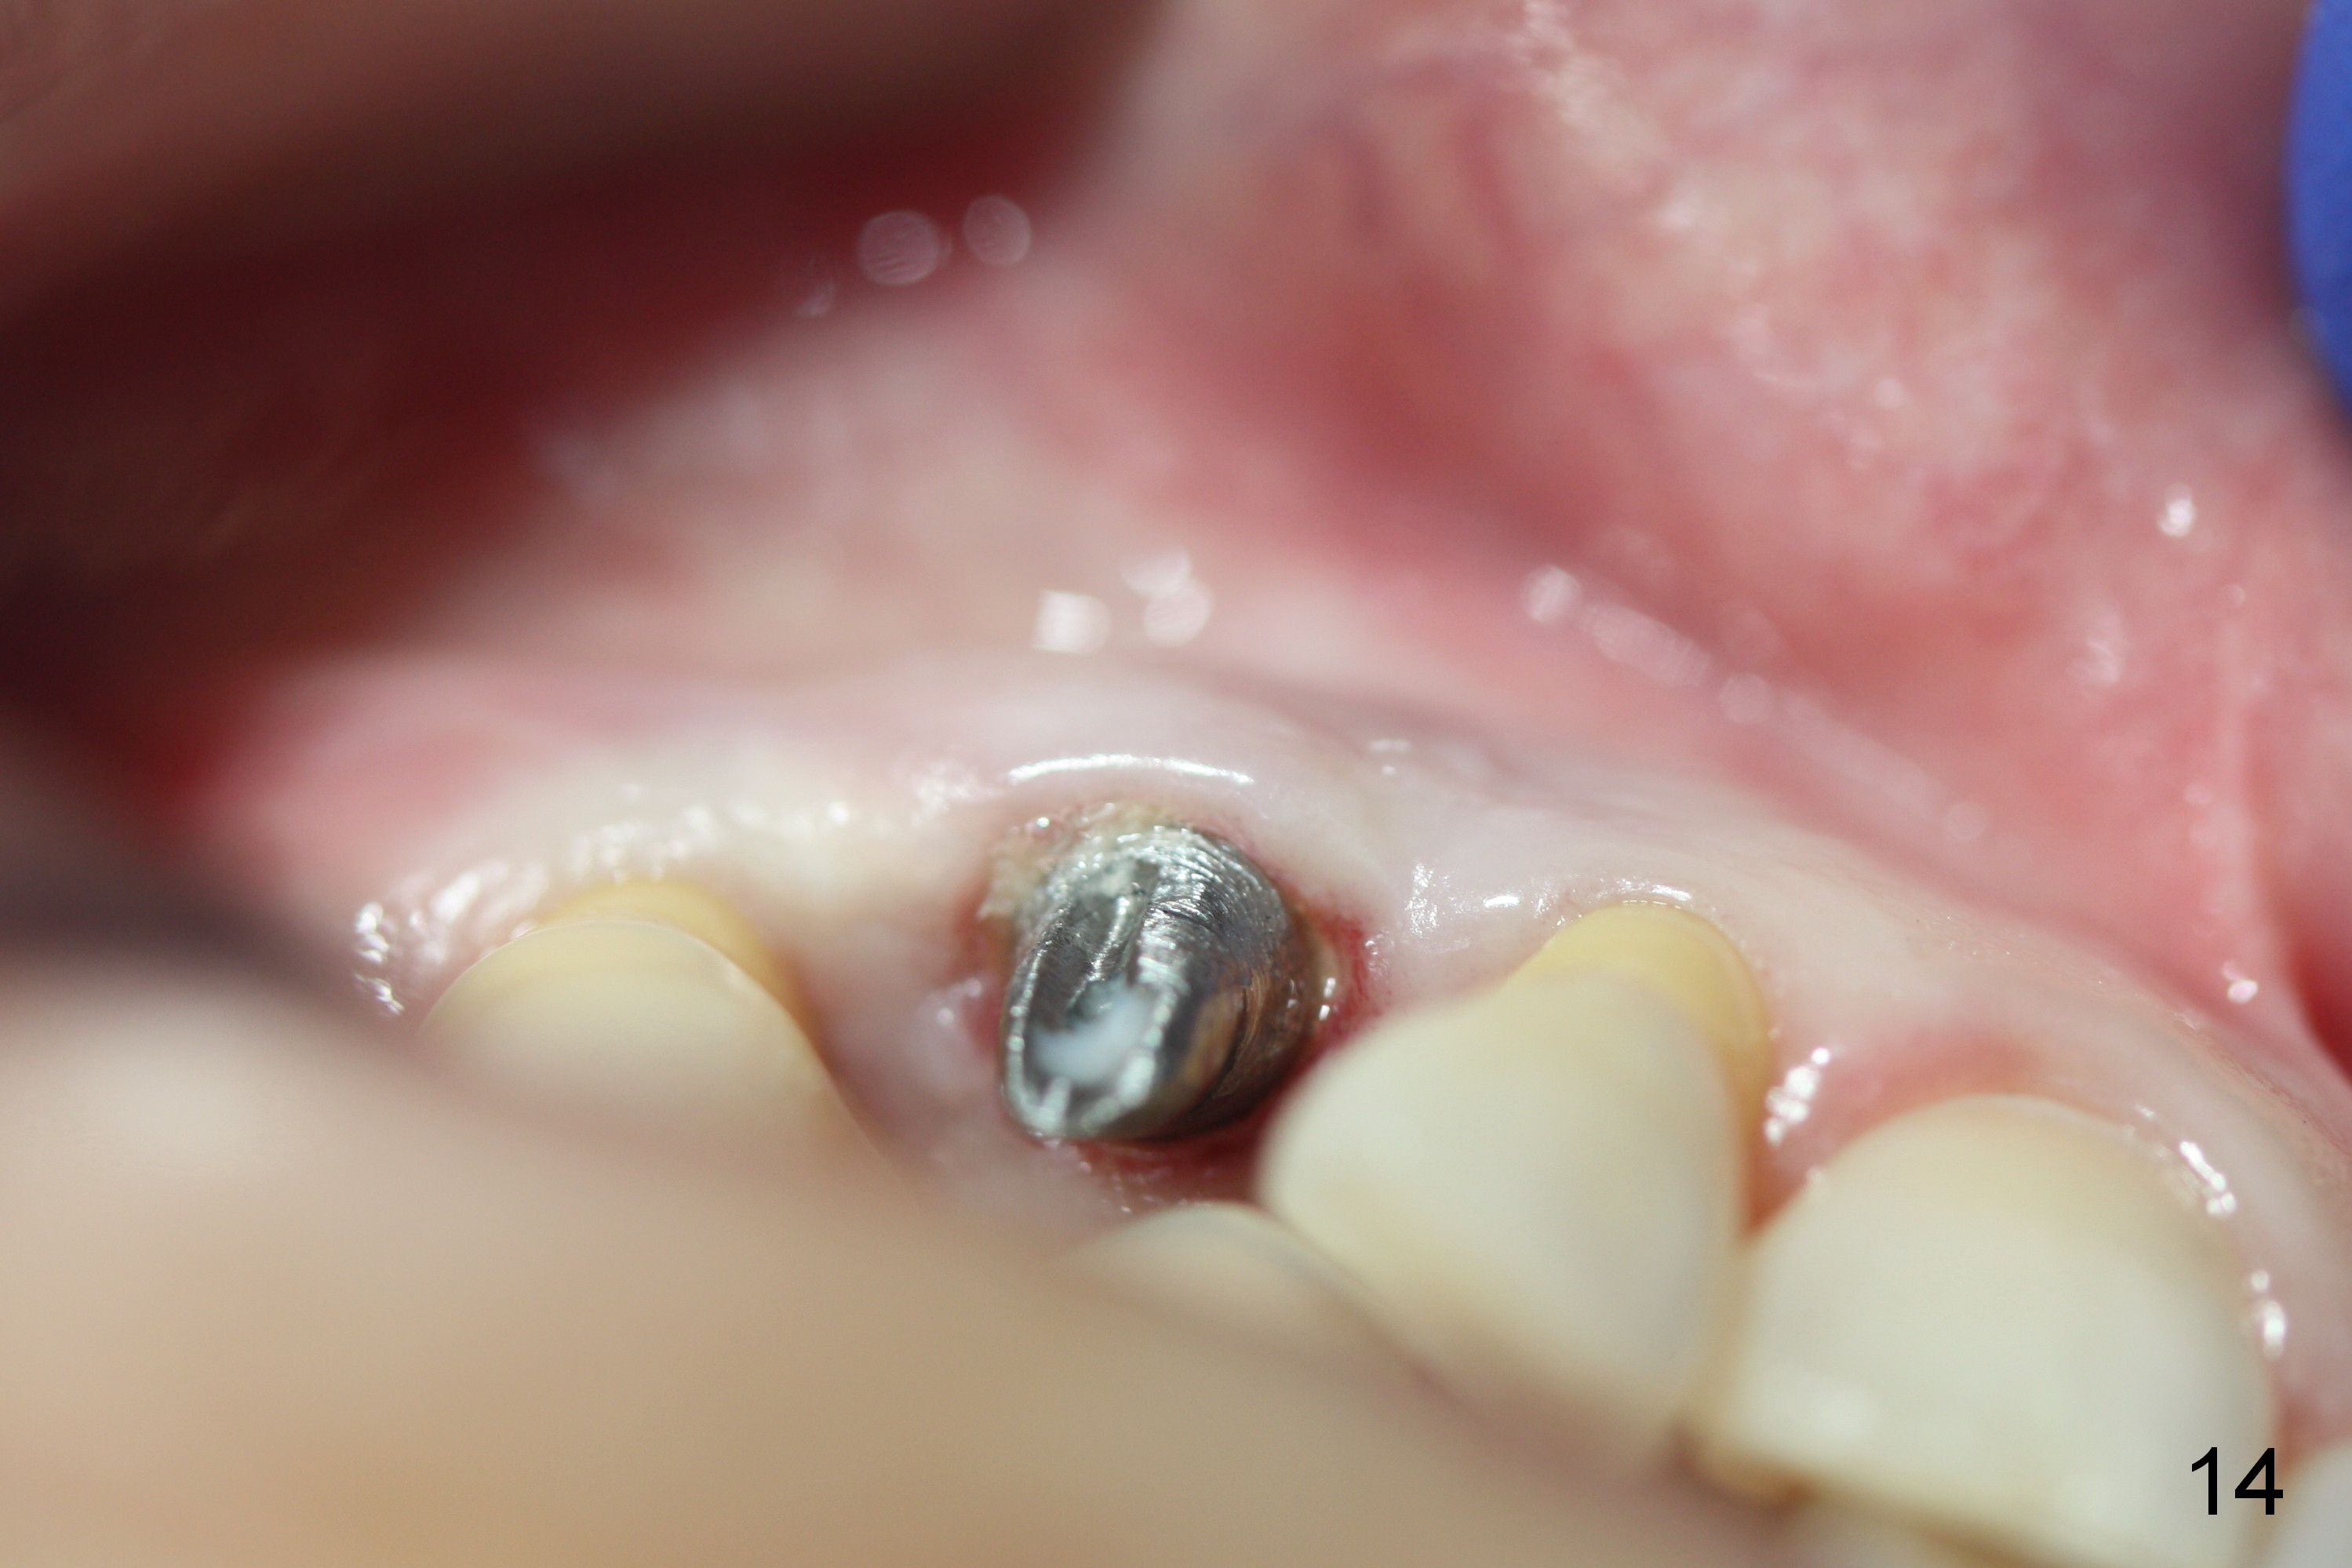

The gingiva is healthy 6 months postop (Fig.13) without buccal plate collapse (Fig.14). The implant and abutment have been prep for final restoration (Fig.15). Although the buccal plate is thin 3 years 5 months post cementation (Fig.16 B), the crest (>) is present, which accounts for no periimplantitis.